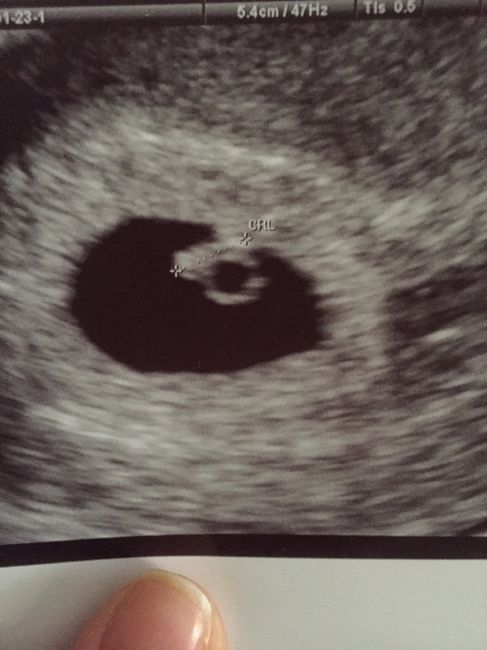

Ciaooo qualcuna ha sentito parlare del metodo Ramzi? A voi ci ha azzeccato o ha sbagliato? Vi metto una foto dell’eco interna a 7+3 “dovrebbe” essere maschio secondo la teoria o sbaglio io a vedere? Altra domandina: l’11 ho fatto il dna fetale (con...